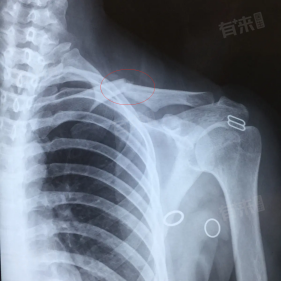

锁骨骨折什么情况下需要手术

1、骨折移位明显:当锁骨骨折后断端出现明显移位,如骨折两端重叠、成角畸形严重等情况时,往往需要手术。显著的移位可能导致骨折愈合困难,即便愈合也易遗留外观畸形,影响肩部美观及正常功能,通过手术可对骨折断端进行复位与固定,促进良好愈合。

3、合并血管神经损伤:一旦锁骨骨折合并有血管、神经损伤,比如骨折端压迫或刺伤附近的锁骨下血管,导致出血不止或影响肢体血液循环,或者损伤臂丛神经,引起上肢麻木、无力等症状。此时手术可在修复骨折的同时,对受损的血管、神经进行探查、修复,避免造成更严重的后果。